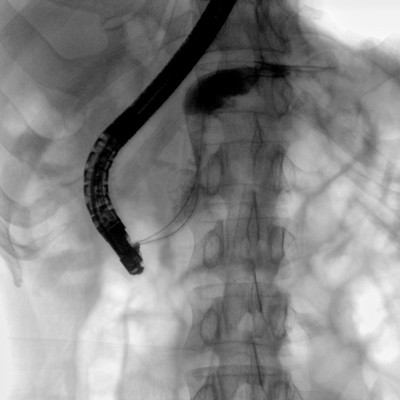

可用于常規(guī)的外周血管介入手術,設備的移動性好,對手術室空間要求低,可滿足長時間X光透視的需求,且增加了獨特的血管影像處理功能,是開展介入手術的理想設備。

優(yōu)質平板探測器、可靈活升降調節(jié)SID、獨特圖像處理系統(tǒng)、高品質濾線柵,大視野成像清晰不失真。

采用智能劑量控制技術,可根據(jù)不同體型和不同部位,準確調節(jié)投照劑量。使操作者在任何使用環(huán)境下,都能實現(xiàn)低劑量、診視圖像清晰的效果。